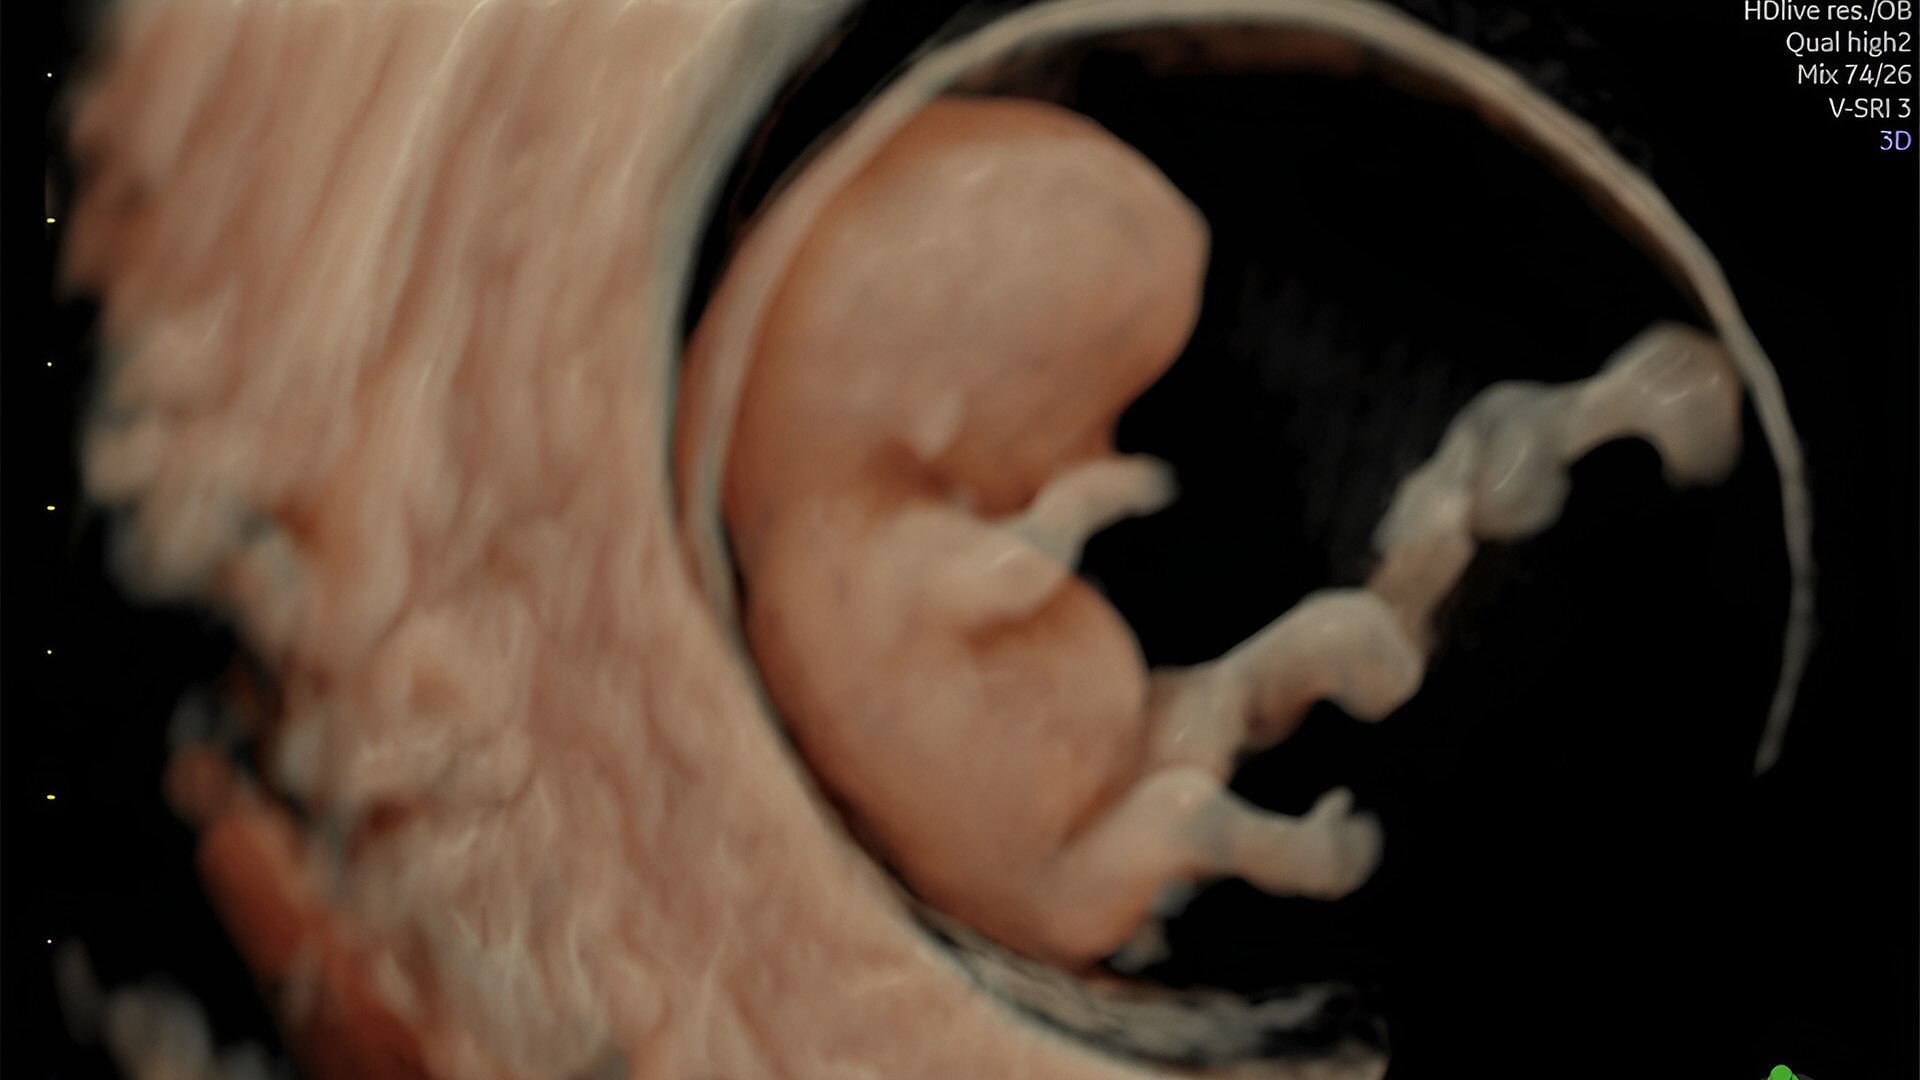

Detect the undetectable

Discover complicated anomalies and pathologies with the Voluson Expert 22 to provide answers sooner for better decision making.

Complex cases come with enough uncertainty. That's why the Voluson Expert 22 is specifically designed for in-depth assessment of complicated anatomy — with pioneering first trimester, fetal cardiac, gynecological, and other pivotal technologies that focus on early detection and intervention.

Identifying fetal cardiac abnormalities earlier means you can intervene sooner, plan for delivery, and potentially improve outcomes. The Voluson Expert 22 provides a full solution of progressive tools, to help distinguish the tiniest structures with stunning clarity to provide patient answers faster.